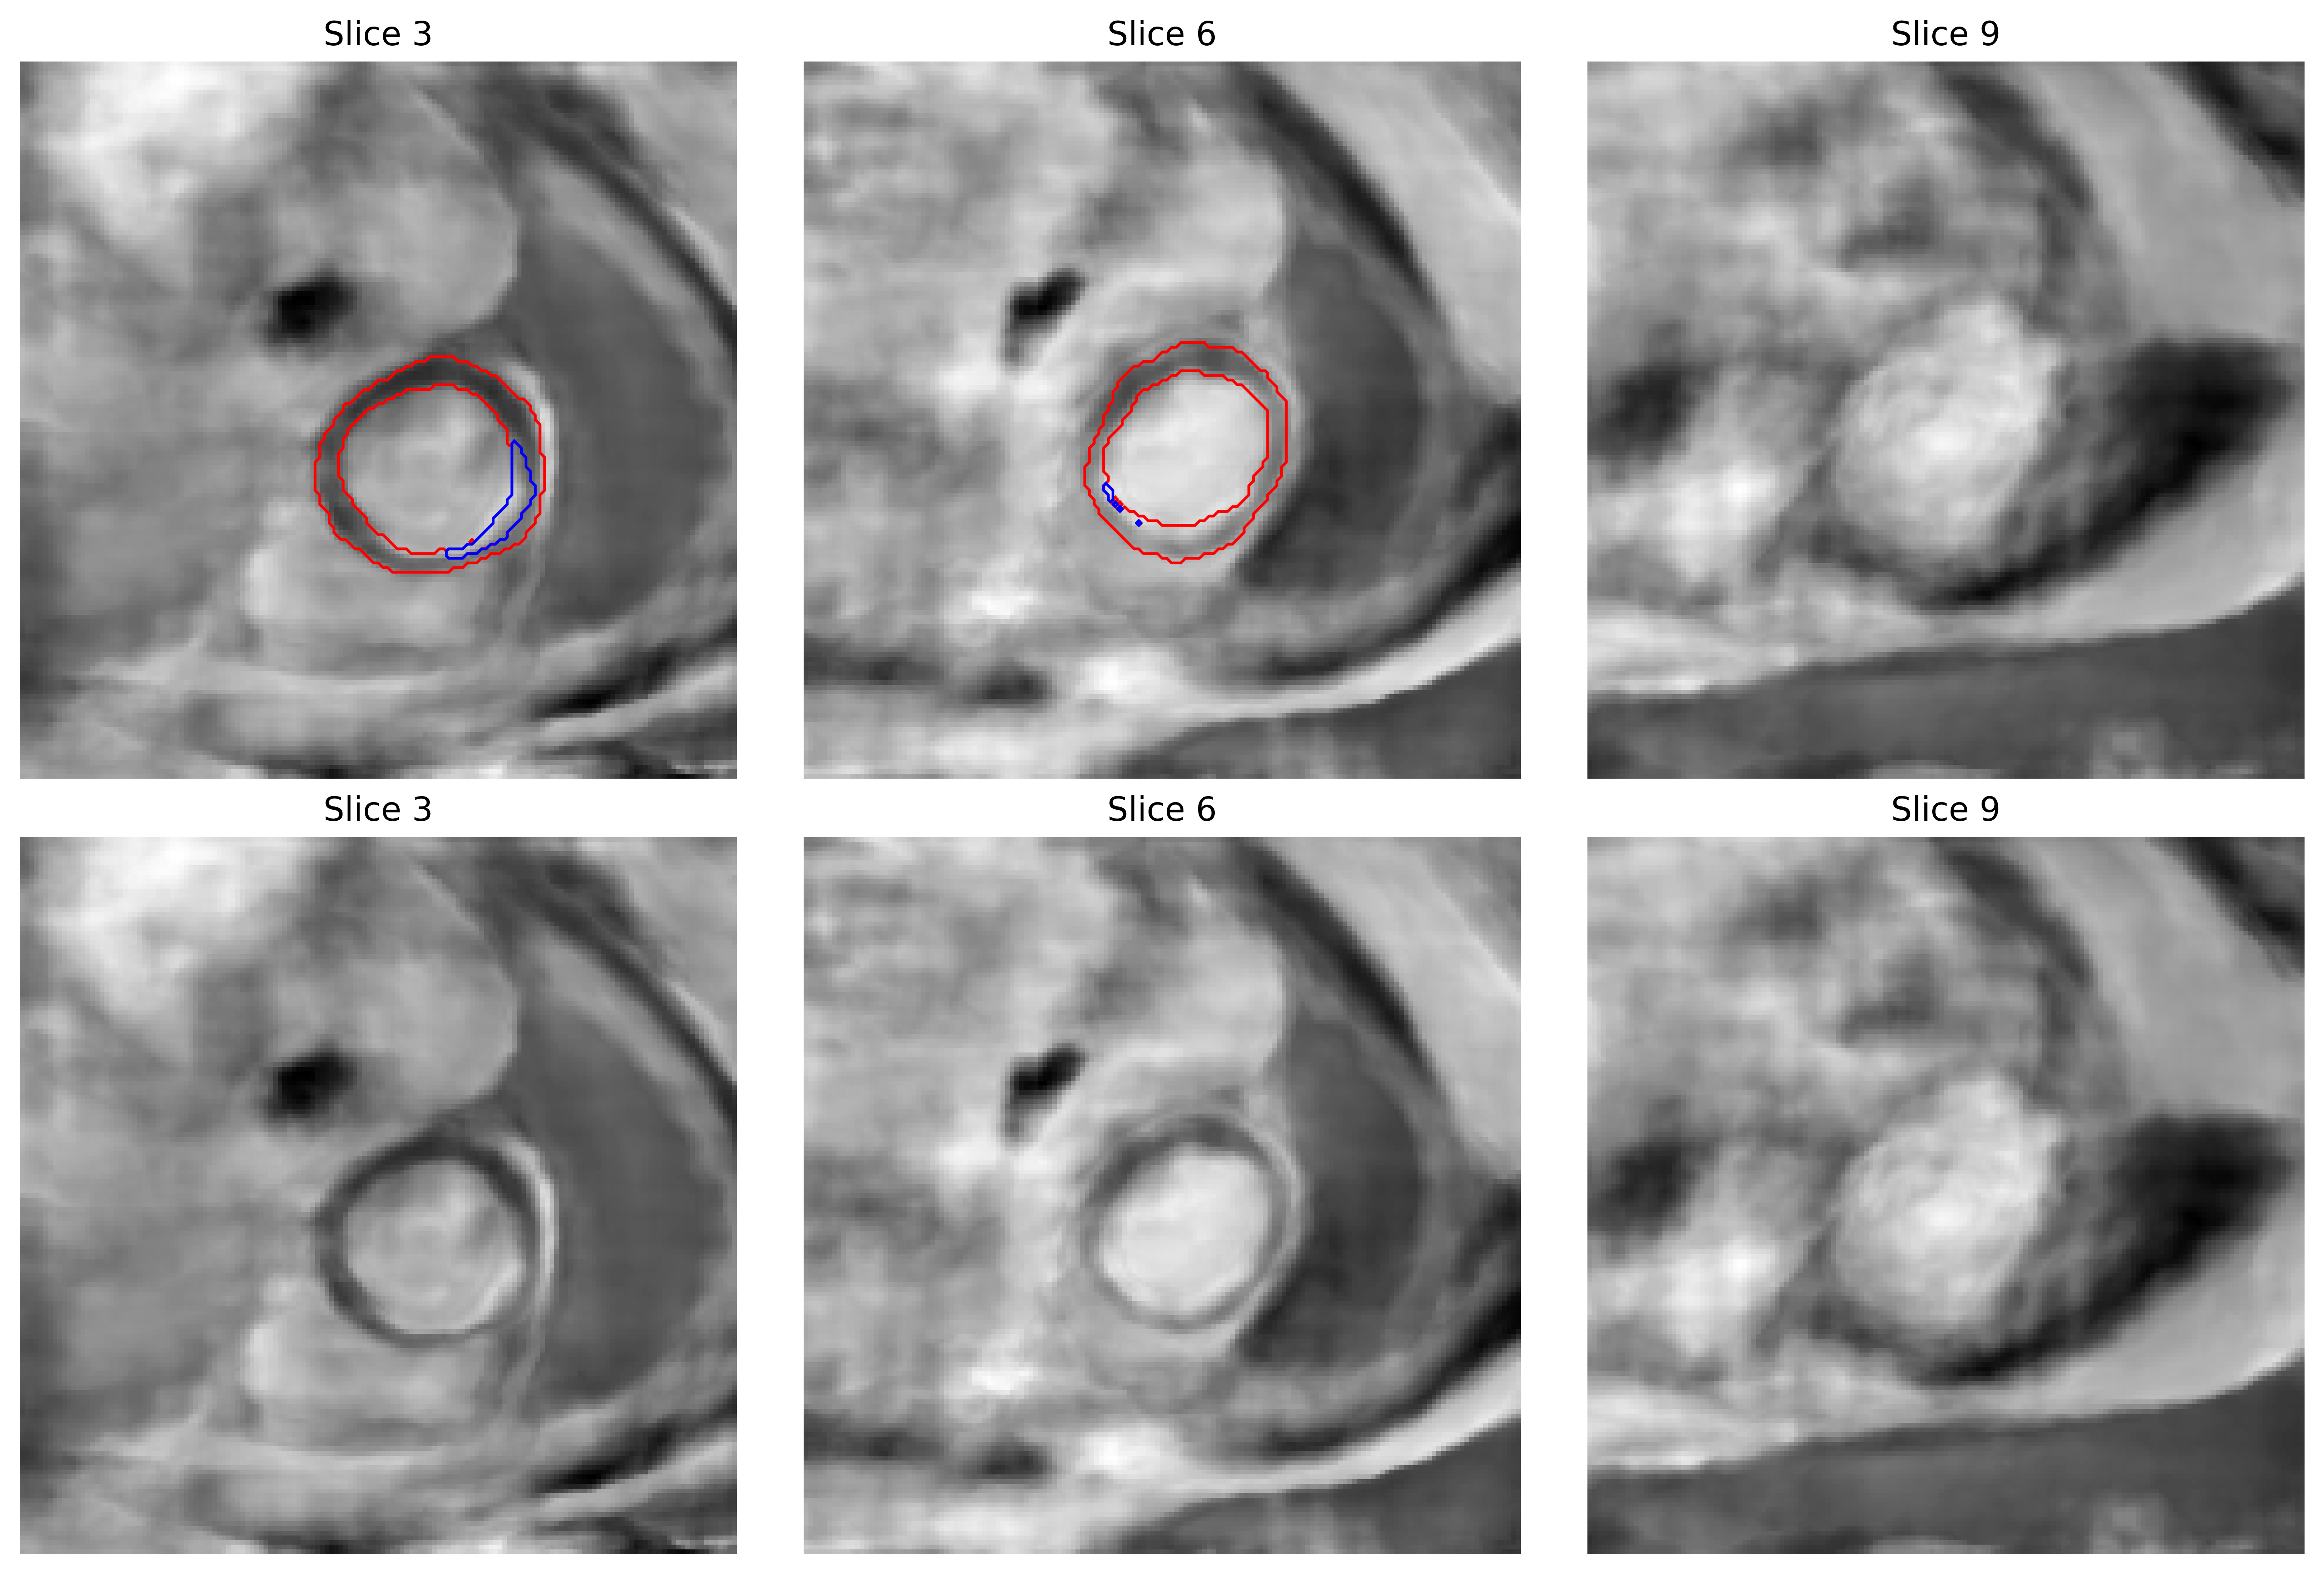

(a) Real LGE slices

(b) Synthetic LGE slices

4.1 Evaluation of Synthesized LGE Images

Figure 2 shows representative examples of real and synthetic LGE short-axis slices at basal, mid-ventricular, and apical levels, with corresponding segmentation contours. Visual inspection shows that the proposed synthesis framework preserves critical anatomical structures relevant for downstream analysis. In particular, the myocardium maintains consistent wall thickness, smooth contours, and coherent geometry across slices, indicating that the latent representation captures global cardiac shape. Fibrosis regions, despite their sparse and heterogeneous appearance in the real data, are generated at anatomically plausible locations within the myocardial wall, i.e., they exhibit realistic spatial relationships relative to surrounding tissue.

While fine-grained texture patterns outside the myocardium are simplified in the synthesized images, this effect is largely confined to regions of limited clinical relevance for scar segmentation. In contrast, areas within the myocardium and fibrosis masks retain higher structural fidelity, which is critical for training segmentation models. This behavior is consistent with the joint image-mask representation learned by the INR, where anatomical structures that are explicitly supervised during training are more accurately preserved than background regions.

By visually examining 2D slices (Figure 2) and 3D volumetric representations (Figure 4), we observe that the proposed framework produces anatomically plausible cardiac structures across the short-axis stack. The synthesized myocardium maintains consistent wall thickness and coherent geometry across slices, while fibrotic regions are generated at anatomically realistic locations within the myocardial wall.